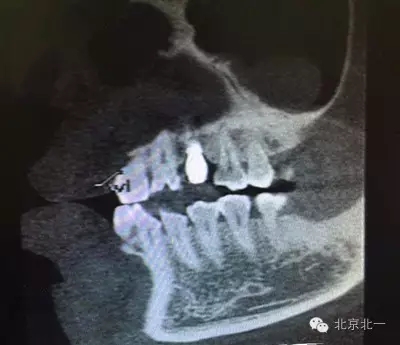

患者種植一月后種植區(qū)不適,偶有疼痛來院拍片發(fā)現(xiàn)23埋伏牙,與種植體相鄰,如圖一、二、三、四所示。

本病例建議:北一種植王明老師建議拔除埋伏牙,并同期植骨,觀察植體情況。提前告知患者失敗等風(fēng)險(xiǎn),簽署同意書。

但是國外文獻(xiàn)卻有不拔除埋伏牙的直接種植病例報(bào)告陳剛博士(本文獻(xiàn)由友睦齒科陳剛博士提供,向陳剛博士致謝。感興趣的醫(yī)生可去下載。)